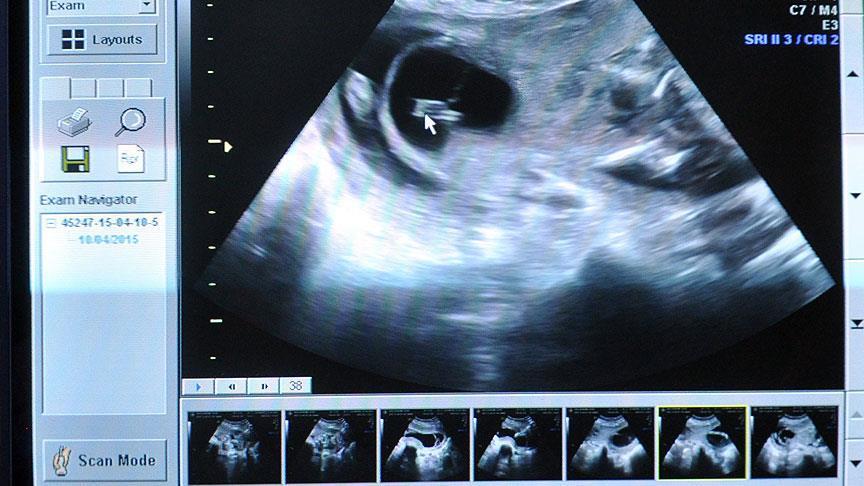

أفادت دراسة أمريكية حديثة، بأن الأطفال الذين يولدون متأخرًا، أى بعد المواعيد الطبيعية لولادة الأم فى الشهر التاسع، لديهم مستويات أعلى من القدرة المعرفية في المدرسة.

وأوضح الباحثون بجامعة نورث ويسترن الأمريكية، أن الأطفال الذين يولدون في الأسبوع الـ 41، سجلوا درجات أعلى فى الاختبارات المعرفية والإدراكية، ونشروا نتائج دراستهم في دورية (JAMA) لطب الأطفال.

وأجرى الباحثون دراستهم على 1.4 مليون طفل في ولاية فلوريدا الأمريكية، وراجعوا سجلاتهم ووجدوا أنهم ولدوا جميعاً بين الأسبوعين 37 و 41 من الحمل، وكان ذلك بين عامي 1994 و 2002.